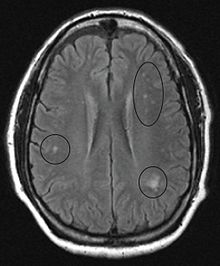

Im Gehirn selbst sind die Veränderungen weniger schwerwiegend. Hier treten kleine, meist subkortikal gelegene Herde mit Nervenfasernverfall und Anhäufung von Astrozyten auf, sowie runde Blutungsherde mit Anlagerung von Gliazellen. Diese pathologischen Veränderungen können auch in der Hinterwurzel des Rückenmarks und, in geringerem Ausmaß, bei peripheren Nerven auftreten. Sie können mittels Magnetresonanztomographie erkannt werden.